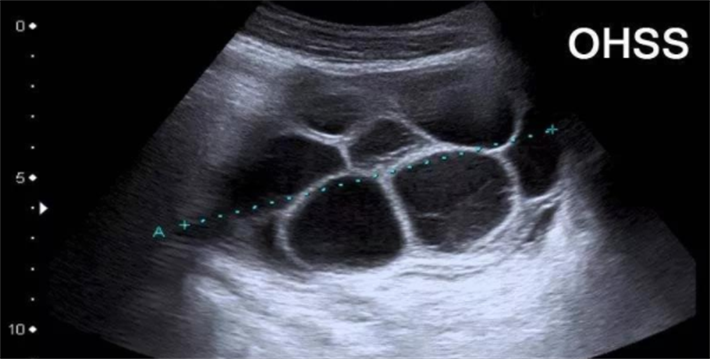

1.卵巢过度刺激综合征

卵巢过度刺激综合征是促排卵过程中较为常见的医源性并发症,其发生与外源性促性腺激素刺激后卵巢过度反应有关。轻度OHSS表现为腹胀、恶心、卵巢增大;中重度OHSS可出现大量腹水、胸水、血液浓缩、电解质紊乱及血栓形成等严重表现。多囊卵巢综合征患者、年轻女性及高AMH水平者是OHSS的高风险人群。

1.促排卵阶段的OHSS预防

OHSS的预防始于促排卵方案的个体化设计。对于OHSS高风险患者,HRC专家会采取以下措施:选择温和刺激或微刺激方案,使用较低起始剂量的促性腺激素;在周期中通过频繁的B超和雌二醇水平监测,动态评估卵巢反应;在触发排卵环节,选择性使用GnRH激动剂替代HCG触发,可降低早发型OHSS的发生率。